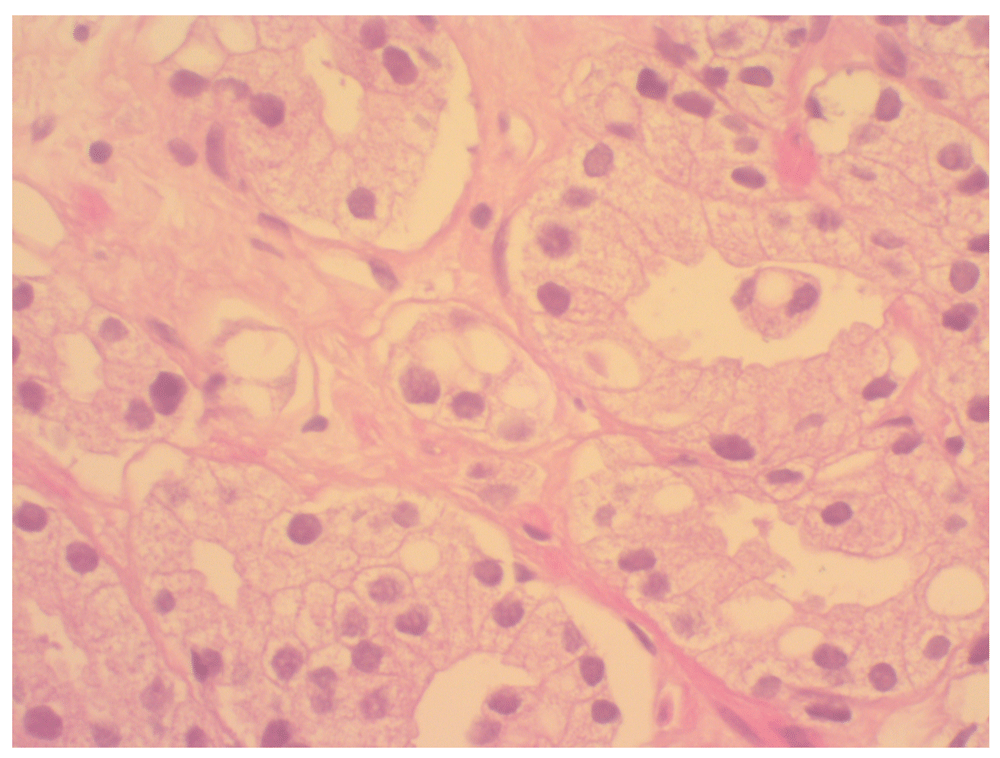

Prostate biopsy. Microscopic examination of the prostate core biopsies demonstrated an invasive prostatic adenocarcinoma. The tumour comprised predominately infiltrative, poorly formed, fused glands, and a minor component of more well differentiated glandular areas that splayed muscle fibres. The poorly formed fused glands were compatible with a Gleason pattern of 4 and the well-formed glands were compatible with a Gleason pattern of 3 (Gleason score = 7; WHO grade group 3). The tumour cells had large nuclei, conspicuous nucleoli and abundant pale eosinophilic cytoplasm. The immunohistochemical profile of the tumour (CK 7 and CK20 negative; PSA monoclonal positive) confirmed primary prostatic origin (Figure 2).

(X400 magnification).